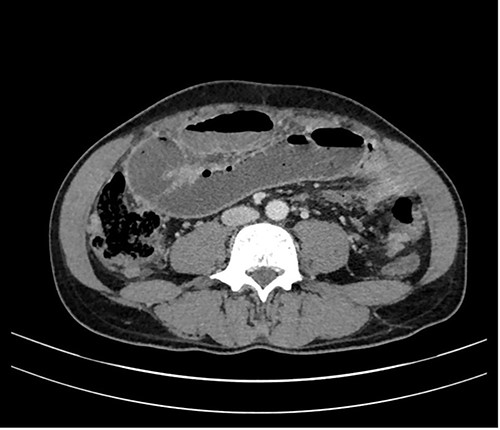

A 53-year-old female of Indian origin, resident in Switzerland for 20 years, presented with diffuse abdominal pain, nausea and meteorism in the primary care consultation. After an initial workup with blood tests and ultrasound (US), a CT of the abdomen was performed (Fig. 3), which revealed enlarged, central necrotic lymph nodes adjacent to the common bile duct (CBD) and the pancreatic head. The enlarged lymph nodes caused an obstruction of the CBD. The patient was referred to our institution for further diagnostic tests.

CT with contrast (A) coronal view and (B) axial view: cystic solid mass in the region of the hepatic hilus with unclear association to the head of the pancreas.